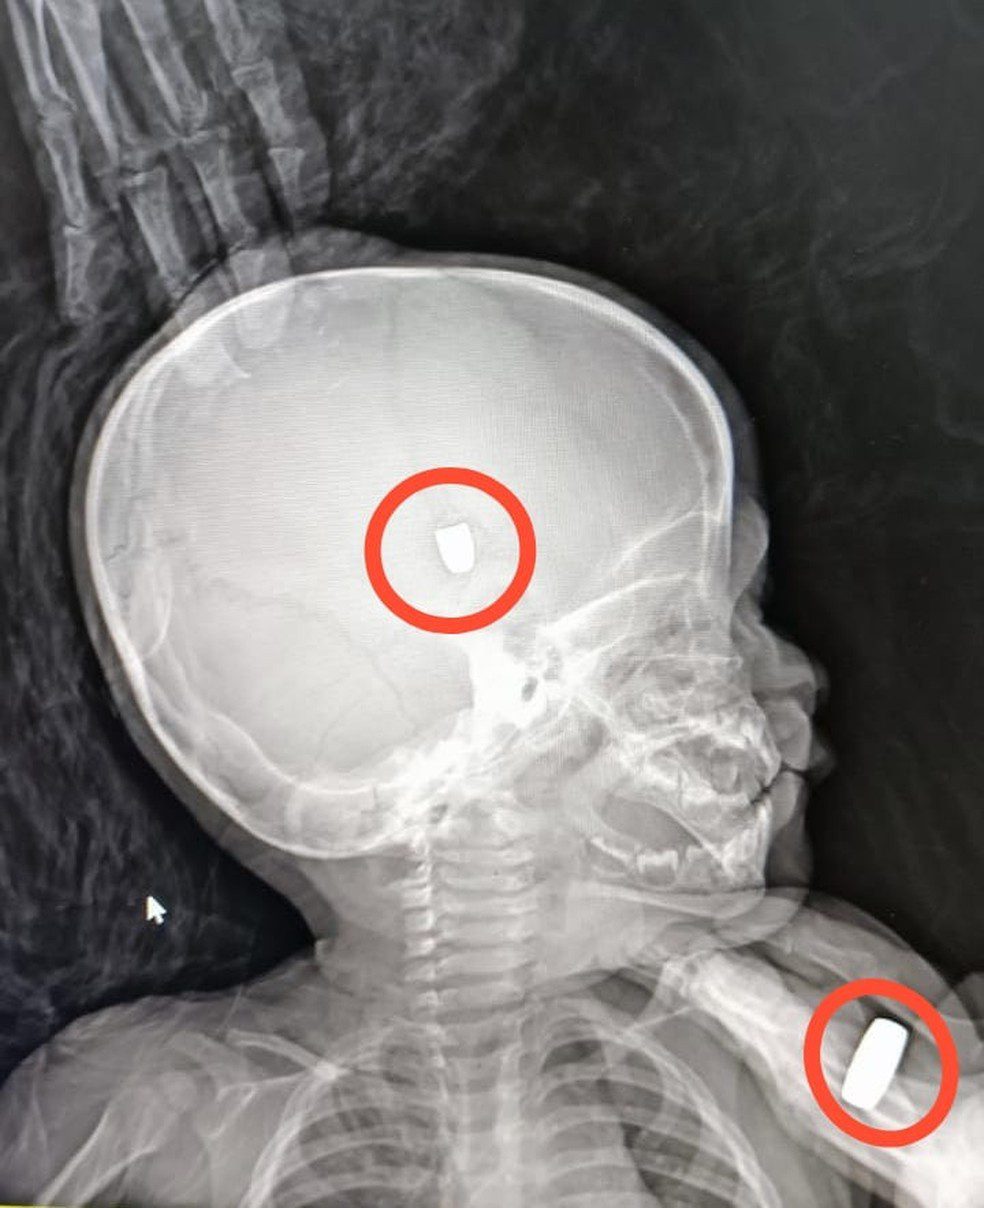

O bebê ficou com um projétil alojado no ombro e outro na cabeça e precisou passar por cirurgia. Ele foi encaminhado para o Hospital Cosme e Damião e depois para uma unidade de saúde particular de Porto Velho. O atual estado de saúde não foi divulgado oficialmente.